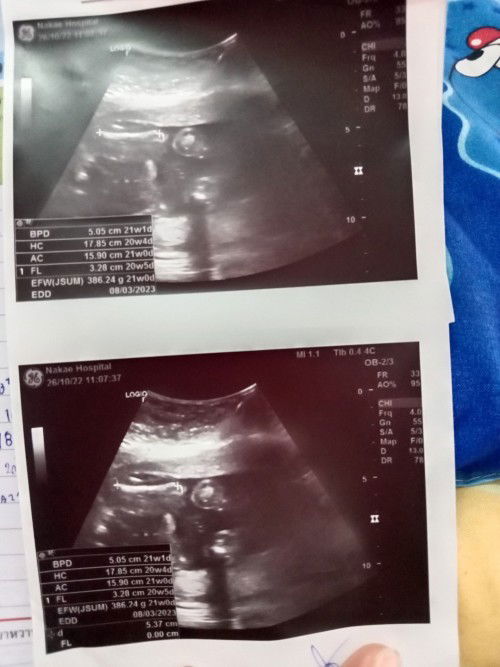

พอจะมองออกไหมคะแม่ๆว่าผู้หญิงหรือผู้ชายมีแต่คนทักว่าจะได้ผู้หญิง#ขอบคุณสำหรับคำตอบค่ะ #ขอคำแนะนำหน่อยค่ะ

น้องอยู่ท่านี้ไม่เห็นเพศเลยค่ะ